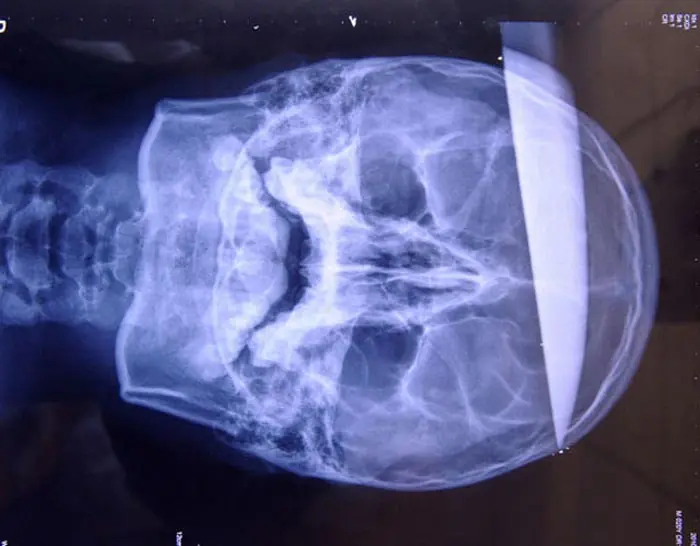

Esto es para no creerlo. Más de alguno de nosotros hemos saltado de rabia al ver a algún jugador haciendo trampa en juegos en linea, pero de ahí a apuñalarlo en la cabeza con un cuchillo carnicero para demostrar nuestro enojo, es como mucho [b]Así sucedió en las afueras de un Cyber Cafe en la provincia de Jilin, donde un adolescente de 17 años terminó con un cuchillo enterrado en su cráneo tras una discusión respecto a de si la víctima utilizaba o no wallhack en Counter Strike.[/b] [b]Lo extraño de todo esto, es que el joven acudió por sus propios medios y obviamente aún consciente a un hospital donde, tras 10 horas de cirugía, lograron remover el cuchillo OXIDADO que tenía incrustado en la cabeza. Actualmente, se encuentra en observación pero parece no haber sufrido daños permanentes a pesar de la profundidad de la herida. Su médico tratante señaló que las posibilidades de sobrevivir a una herida de esta naturaleza son de 1 en 10 Mil.[/b] [b]¿Creo que esto es mucho no? esto quiere decir que han estado jugando mucho Counter [/b] [b]A este joven, claramente se lo filetearon, demostrando que no solo aquí en Latino América los CounterPlayers son adictos[/b]